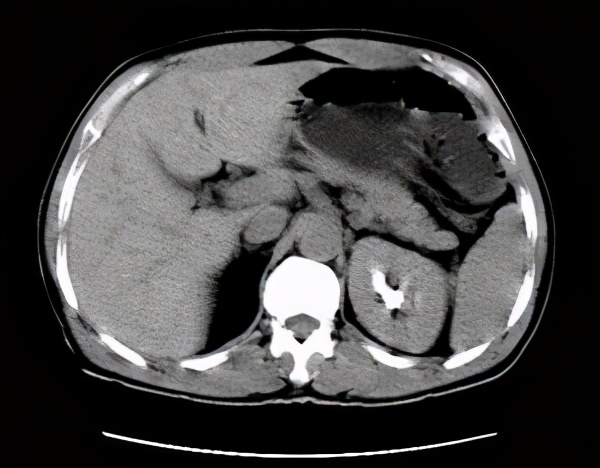

2)CT/CTU: 可以帮助诊断结石、泌尿系肿瘤、了解肾积水和肾实质萎缩情况,肾功能正常且需要进一步明确诊断的患者,是推荐的无创检查。

CT可更加清晰的了解肾脏、输尿管及周围组织脏器的情况